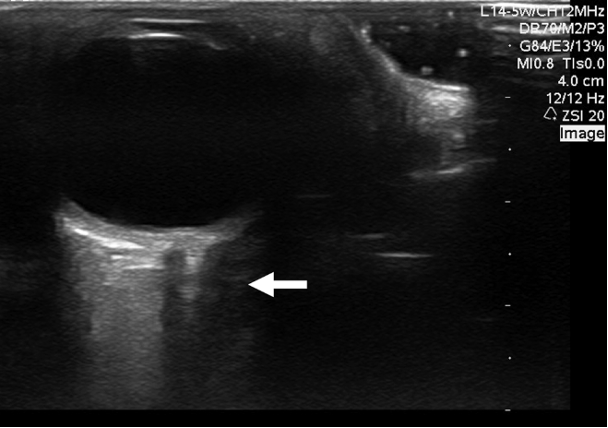

Figure 1ab: LV levels in the PLAX view (a) and A4C (b) in cardiology convention